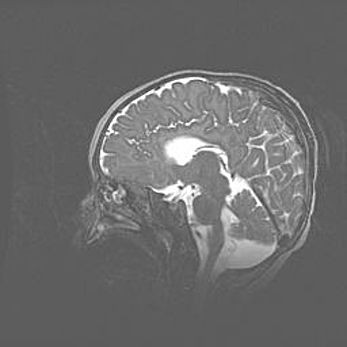

Сообщающаяся гидроцефалия. Кистозная энцефаломаляция головного мозга.

Возраст: 3 месяца 4 дня

Вес: 3100 г

Пол: женский

Окружность головы: 34 см

Срок гестации: 31 неделя

Кистозная энцефаломаляция головного мозга - одна из форм поражения головного мозга в детском возрасте. Характеризуется возникновением множественных и распространённых кист в коре, белом веществе и подкорковых образованиях головного мозга у плодов, новорождённых и детей раннего возраста. Развитие кистозной энцефаломаляции связано с внутриутробной асфиксией и гипотонией, родовой травмой, тромбозом синусов, пороками развития сосудов, инфекциями, сепсисом и другими причинами. Наиболее значимые инфекционные агенты: вирусы простого герпеса, цитомегалии, краснухи, токсоплазмы, энтеробактерии, золотистый стафилококк и другие.